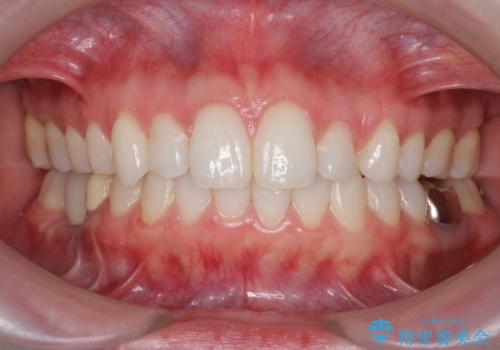

- 前歯のがたつきを主訴に来院。

前歯が引っ込んでいると、そこが影になり大変目立ちます。

矯正治療で大きく見た目を改善することが可能です。